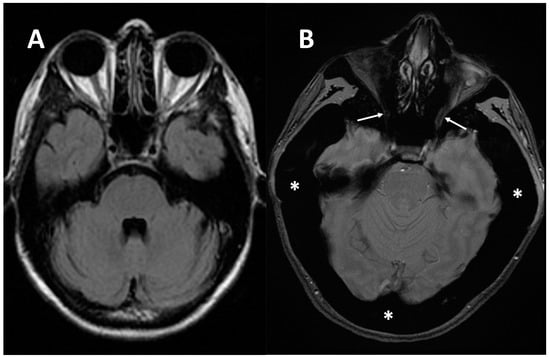

Another common group of complications is neurological involvement, which can be found in patients with ARO or IAO osteopetrosis. Imaging tools, MRIs above all, play a key role in the detection, evaluation, and follow up of neural structures damage. MRI is fundamental to assess cranial foramina (Figure 6) and brain abnormalities.

Figure 6. (A) axial MRI of a healthy young female (shown as comparison). (B) axial MRI (T2w*) of a 38-year-old female with a clinical-radiological diagnosis of osteopetrosis (ARO type); narrowing of both optic foramens can be noted (arrows) caused by a diffuse bone thickening. Diffuse bone thickening of cranial bones is associated with a marked ipointense signal intensity of all the skeletal structures related to the diffuse bone sclerosis (asterisks).